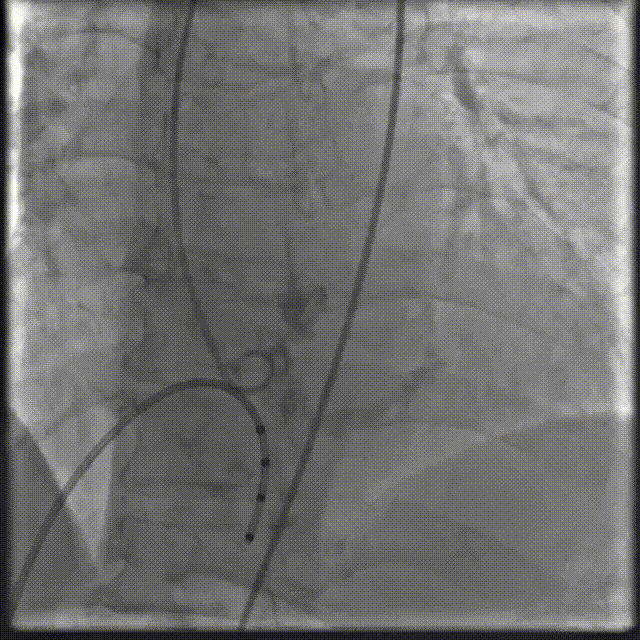

2.20mm球囊预扩,无腰征无返流,证实选择偏小一号的人工瓣膜(downsize策略)的可行性。

图A、B 术前CT检查及术中影像均可见明显钙化团块(箭头所示),图C、D:球囊预扩张及人工瓣膜植入过程中均可见钙化团块明显移位(箭头所示)。